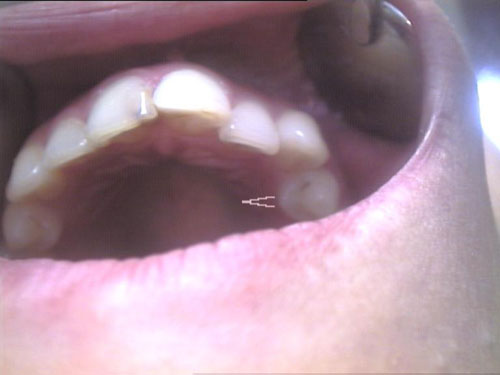

Zahn-Anomalien 1

Zahn-Anomalien 2

Zahn-Anomalien 3

Zahn-Anomalien 4

Zahn-Anomalien 5